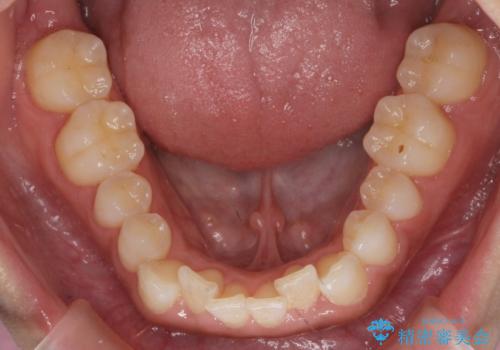

八重歯を非抜歯で マウスピースで治療 奥歯を後ろに下げてすき間を確保

- 八重歯を主訴に来院。

奥歯を後ろに下げてすき間を確保し、八重歯を引っ込めて並べる治療を行いました。